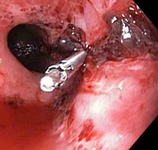

Três clipes tipo "through-the-scope" para o fechamento completo do defeito na mucosa

Do acervo de Juan Carlos Munoz, MD, University of Florida